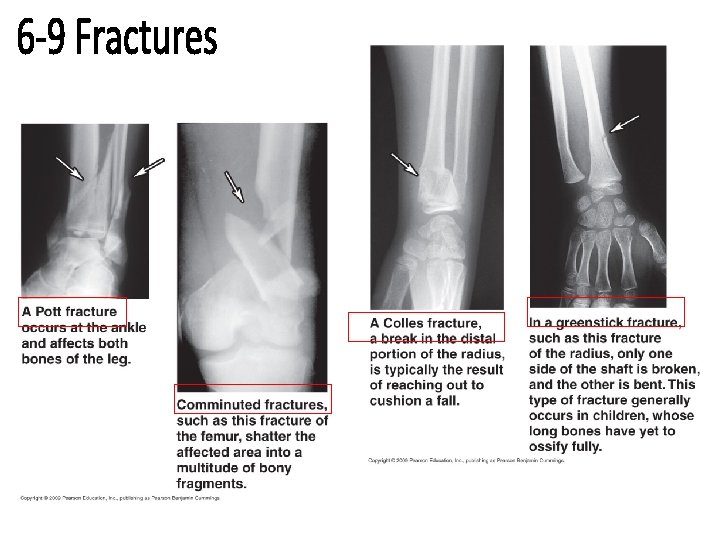

Fractures 1. Open/Compound- through the skin 2. Closed/ Simple- not through the skin 3. Comminuted- smaller fragments 4. Greenstick- only children, 1 side broken, 1 side bends • 5. Impacted- bone through bone • Stress fracture- microscopic , repeated stress • • • can withstand 24, 000 lbs/sq in, 4 x greater than steel

Transverse- break along shaft Spiral- from twisting Displaced- produces abnormal bone alignment